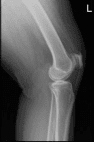

She presented her Xray results, for her left knee there are mild osteoarthritic degenerative changes. For the right knee, there are moderate osteoarthritic degenerative changes. There are no fractures and there are no acute fractures.

Left knee X-ray